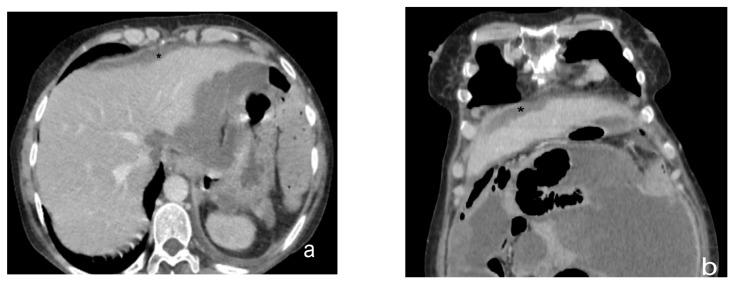

Peritoneal carcinosis is a condition characterized by the spread of cancer cells to the peritoneum, which is the thin membrane that lines the abdominal cavity. It is a serious condition that can result from many different types of cancer, including ovarian, colon, stomach, pancreatic, and appendix cancer. The diagnosis and quantification of lesions in peritoneal carcinosis are critical in the management of patients with the condition, and imaging plays a central role in this process. Radiologists play a vital role in the multidisciplinary management of patients with peritoneal carcinosis. They need to have a thorough understanding of the pathophysiology of the condition, the underlying neoplasms, and the typical imaging findings. In addition, they need to be aware of the differential diagnoses and the advantages and disadvantages of the various imaging methods available. Imaging plays a central role in the diagnosis and quantification of lesions, and radiologists play a critical role in this process. Ultrasound, computed tomography, magnetic resonance, and PET/CT scans are used to diagnose peritoneal carcinosis. Each imaging procedure has advantages and disadvantages, and particular imaging techniques are recommended based on patient conditions. Our aim is to provide knowledge to radiologists regarding appropriate techniques, imaging findings, differential diagnoses, and treatment options. With the advent of AI in oncology, the future of precision medicine appears promising, and the interconnection between structured reporting and AI is likely to improve diagnostic accuracy and treatment outcomes for patients with peritoneal carcinosis.

腹膜癌是一种以癌细胞扩散至腹膜为特征的病症,腹膜是衬于腹腔的一层薄膜。它是一种严重的病症,可由多种不同类型的癌症引发,包括卵巢癌、结肠癌、胃癌、胰腺癌和阑尾癌。腹膜癌中病变的诊断和定量对于该病症患者的管理至关重要,而影像学在这一过程中发挥着核心作用。放射科医生在腹膜癌患者的多学科管理中起着至关重要的作用。他们需要对该病症的病理生理学、潜在肿瘤以及典型的影像学表现有透彻的了解。此外,他们需要知晓鉴别诊断以及各种可用影像学方法的优缺点。影像学在病变的诊断和定量中起着核心作用,放射科医生在这一过程中起着关键作用。超声、计算机断层扫描、磁共振成像和正电子发射断层显像/计算机断层扫描(PET/CT)用于诊断腹膜癌。每种成像检查都有其优缺点,会根据患者情况推荐特定的成像技术。我们的目的是向放射科医生提供有关合适技术、影像学表现、鉴别诊断和治疗方案的知识。随着人工智能在肿瘤学中的出现,精准医学的未来似乎很有前景,结构化报告与人工智能之间的相互联系可能会提高腹膜癌患者的诊断准确性和治疗效果。